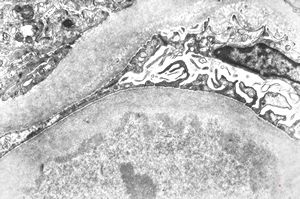

normal kidney - mouse(endothelium and podocytes)

normal kidney - mouse(endothelium and podocyte)